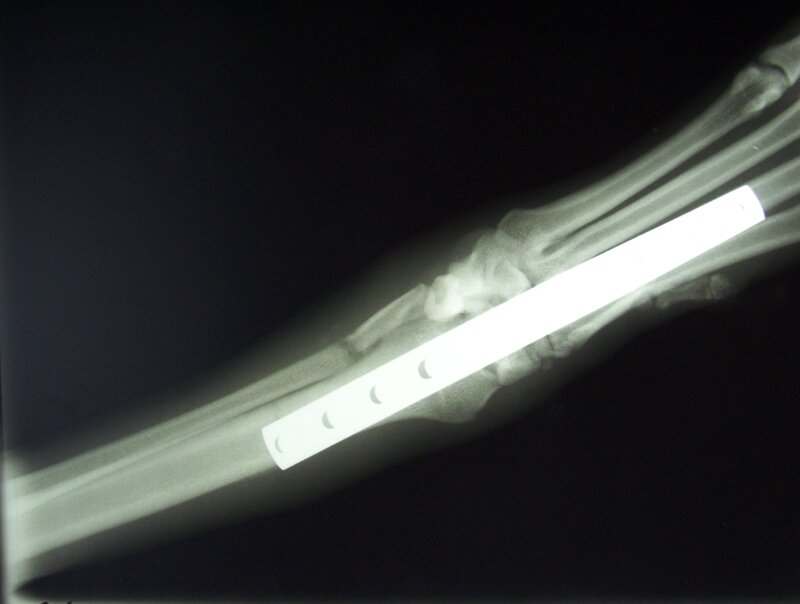

En la reparación de fracturas utiliza de forma habitual osteosíntesis mediante placas de compresión y tornillos, clavos cerrojados o técnicas tridimensionales de fijación externa.